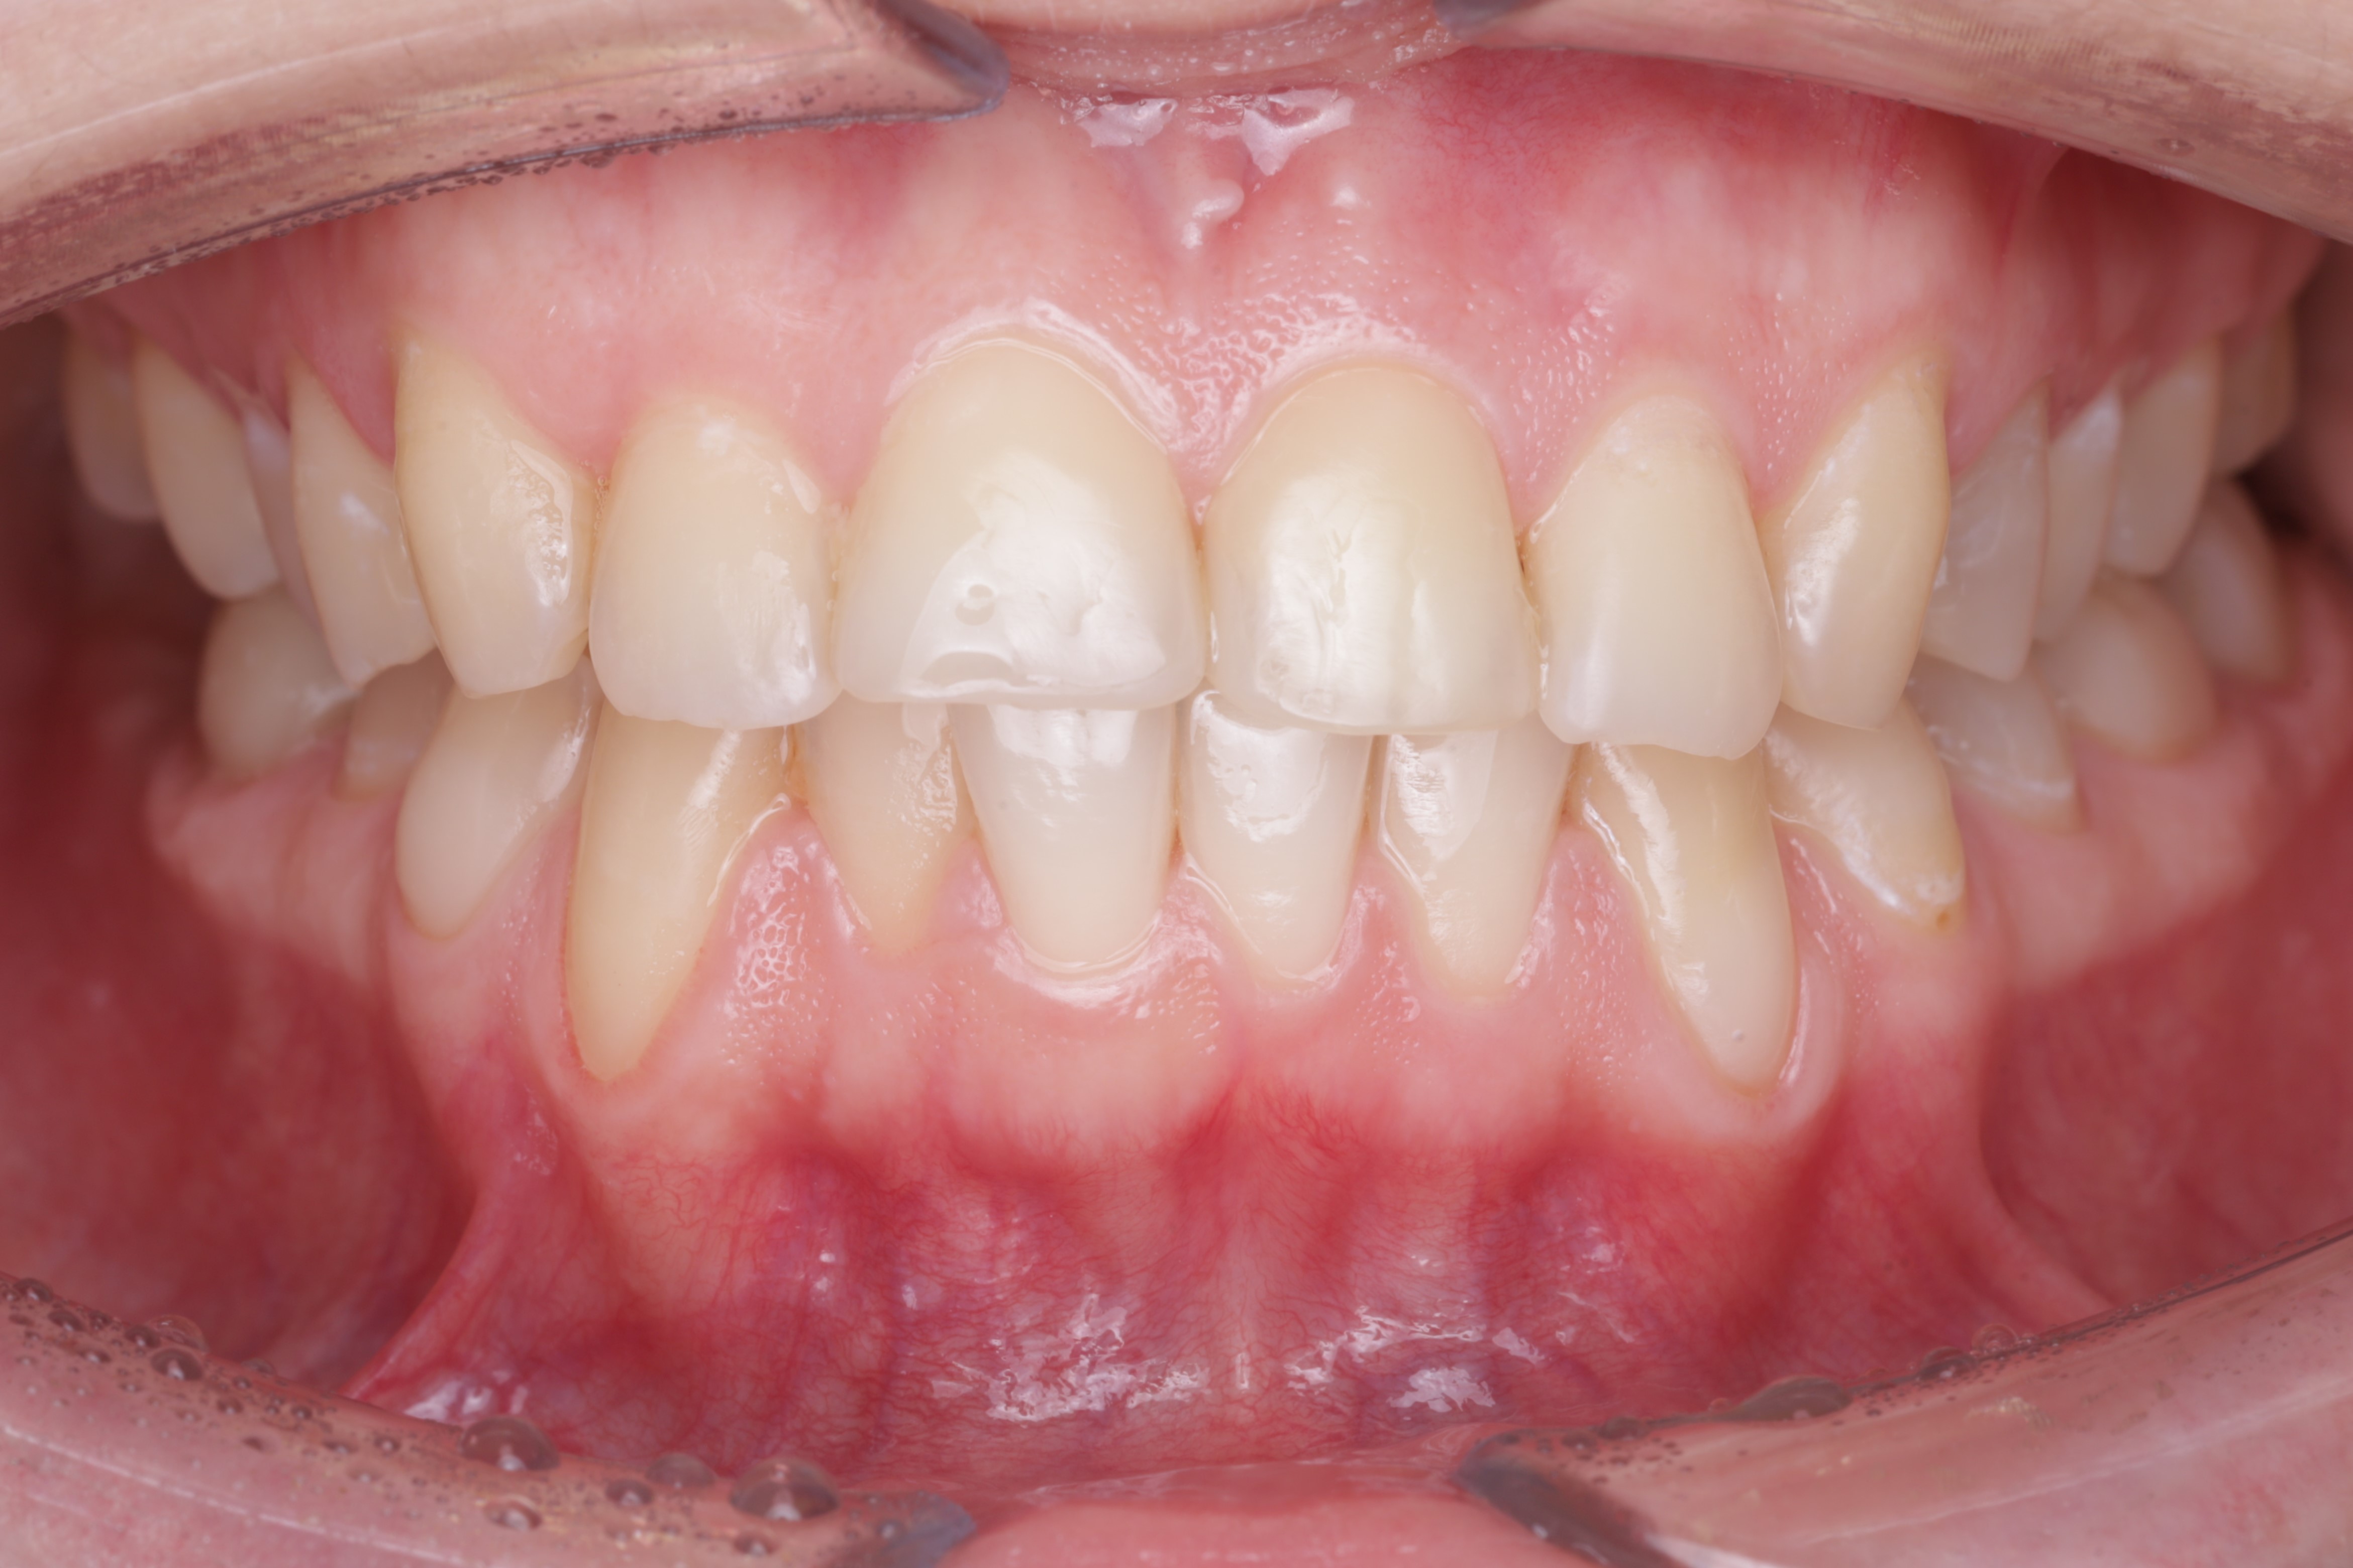

Спустя два месяца ортодонт зафиксировал брекеты. Мы видим полное закрытие рецессий и увеличение толщины десны. Это делает ортодонтическое лечение безопасным, а вероятность возникновения рецессий десны в дальнейшем — минимальной или практически невозможной

Осмотр спустя 6 месяцев :

Мы видим полное закрытие рецессий, увеличение толщины десны, что в дальнейшем делают ортодонтию безопасной, вероятность возникновения рецессий десны в дальнейшем минимальным или практически невозможным.